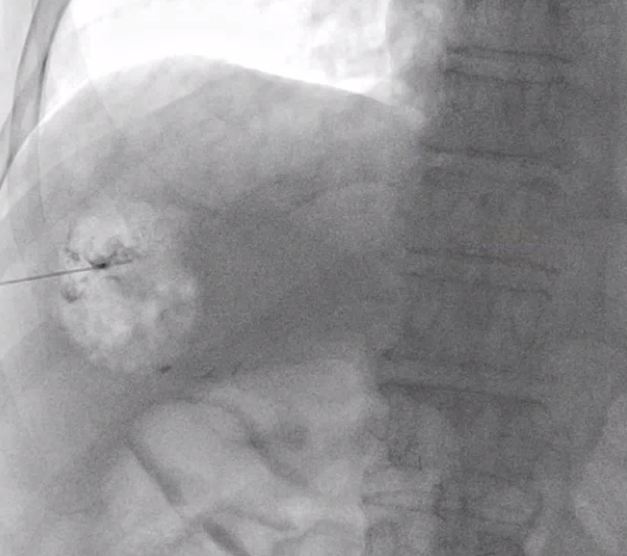

이 바늘은 뚜껑같은 게 있어서 찌르고 난 뒤에 바늘 구멍을 통해 조영제를 주입할 수도 있고 매우 가느다란 철사(와이어)를 넣을 수도 있습니다.

그래서 바늘의 뒷 부분 뚜껑을 열고 조영제를 조금 주입해서 바늘이 목표한 병변 안으로 들어갔는지 확인합니다.

잘 들어갔다는 게 확인되면 아주 가느다란 철사를 넣습니다. 이 철사의 이름은 hair wire 입니다. 마치 머리카락 처럼 가느다랗기 때문이죠.

hair wire 를 넣은 뒤에는 introducer sheath 그 다음엔 앞서 말한 hair wire 보다 조금 굵은 철사가 들어갑니다.

마지막으로 굵은 철사를 따라 배액관이 들어갑니다.